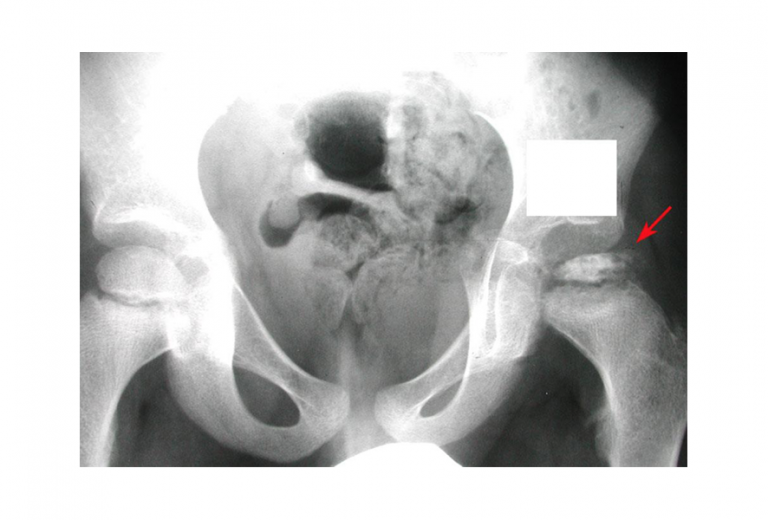

Legg Calves Perthes . Find out how to stage. During the physical exam, your healthcare professional might move your child's legs into various positions to check range of. Perthes disease is a rare childhood condition that affects the hip and causes bone death in the femoral head. Learn about the symptoms, stages, causes, diagnosis, and treatment. It starts when the head of the. It occurs when the blood supply to the femoral.